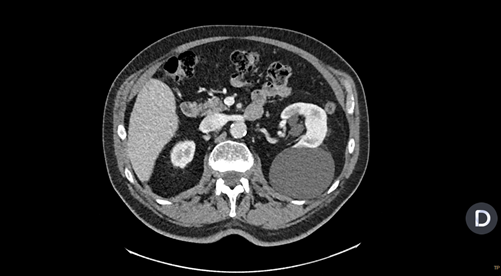

Consulta a urgencies por otro motivo no relacionado con el motivo de consulta por el cual se le realiza un TC torácico y revisando las imágenes se observa una imagen redondeada de márgenes bien delimitados dependiente de riñón izquierdo y que contacta con musculatura paravertebral y costal izquierda.